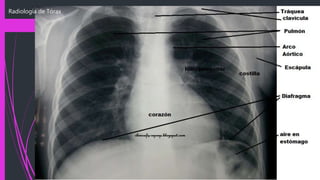

Radiología de Tórax

Tráquea y

Bronquios

La tráquea como una estructura vertical, situada en la línea

media y es desplazada levemente desde la carina hacia la

derecha por la posición del arco aórtico.